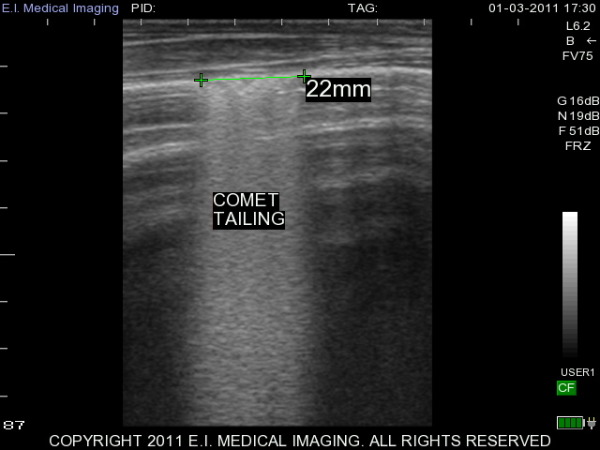

My name is Elizabeth Adams and I am a dairy practitioner in the central valley of California. Recently, I was able to use the IBEX PRO portable ultrasound to look at calf lungs for evidence of damage from calfhood pneumonia. In veterinary school, I scanned all of my patients with respiratory symptoms because it is a fast, non-invasive exam that provides a lot of information quickly. With ultrasound I can see healthy lungs, pleural effusion, atelectasis, consolidation and abscessation.

Ultrasound allows me to look at the surface of the lung; in a healthy lung, this is all we can see as the lung is full of air and doing its job. In a diseased lung, the surface of the lung is abnormal and allows penetration of the ultrasound waves deep into the lung parenchyma. Young calves require only the penetration of a 5-7.5MHz rectal ultrasound probe to see the evidence of damage from previous pneumonia.